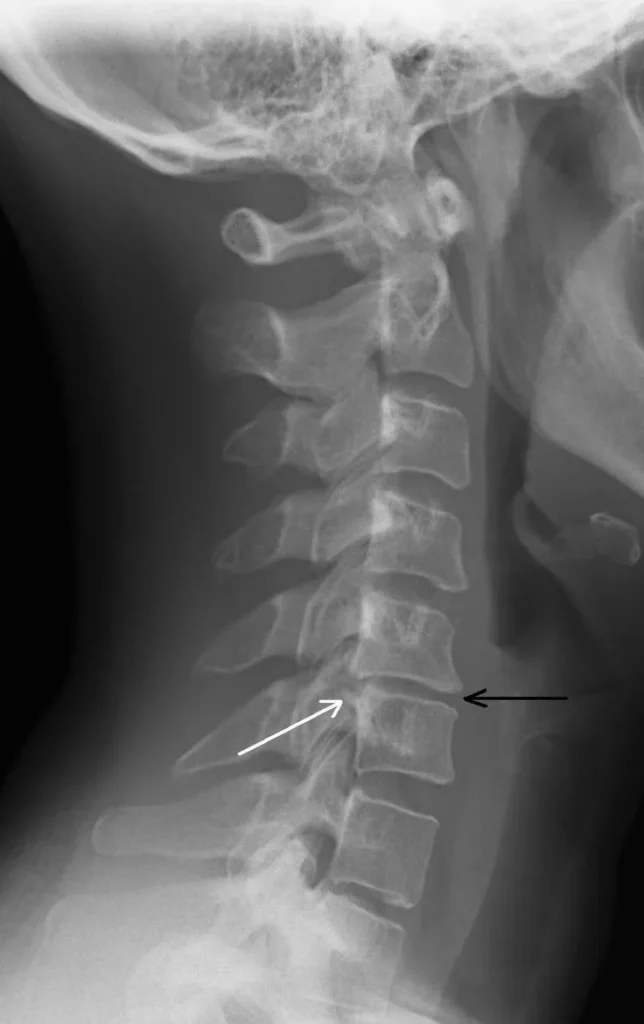

Most acute neck pain is first treated conservatively without imaging. X-rays or MRI are ordered if red flags are present or if pain persists beyond 6–8 weeks despite therapy.

X-rays can reveal fractures, alignment issues, or severe arthritis.

MRI is used when nerve compression, disc herniation, or soft-tissue injury is suspected.

Over time, normal wear-and-tear affects the cervical spine. Intervertebral discs can bulge or herniate, facet joints can develop arthritis, and bone spurs (osteophytes) can form on vertebrae. This process is called cervical spondylosis.

It is very common: nearly 50% of people over age 50 show signs of cervical spondylosis on X-rays. However, the extent of radiologic changes does not always match symptoms.

Degenerative changes can narrow the spinal canal or neural foramina, irritating nerves.